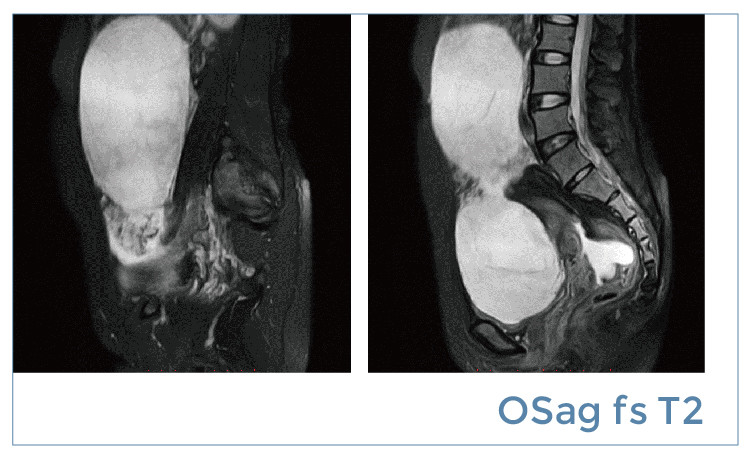

【朗润影像档案】20190419磁共振影像病例结果讨论